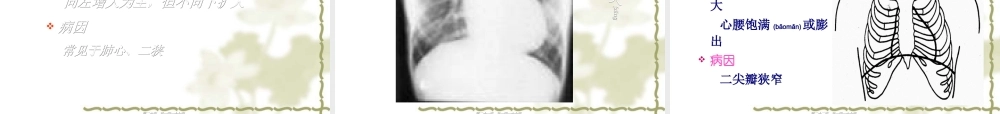

心脏心脏(xīnzàng)(xīnzàng)检检查查河南中医学院河南中医学院第一临床医学院第一临床医学院诊断诊断(zhěnduàn)(zhěnduàn)学科卢依学科卢依平平第一页,共一百一十七页。第一页,共一百一十七页。第二页,共一百一十七页。第二页,共一百一十七页。1.掌握第1、2心音产生机理、鉴别。第三页,共一百一十七页。第三页,共一百一十七页。心脏心脏视诊视诊内容内心前区外形心前区外形第四页,共一百一十七页。第四页,共一百一十七页。(gǔgé)第五页,共一百一十七页。第五页,共一百一十七页。(fànwéi)第六页,共一百一十七页。第六页,共一百一十七页。位置改变位置改变第七页,共一百一十七页。第七页,共一百一十七页。(gāoyā)第八页,共一百一十七页。第八页,共一百一十七页。心尖搏动心尖搏动第九页,共一百一十七页。第九页,共一百一十七页。临床意义证实视诊所见的异常搏动第十页,共一百一十七页。第十页,共一百一十七页。产生机制血流旋涡引起低频较强震动第十一页,共一百一十七页。第十一页,共一百一十七页。--------------------------------------第十二页,共一百一十七页。第十二页,共一百一十七页。(xiāoshī)第十三页,共一百一十七页。第十三页,共一百一十七页。第十四页,共一百一十七页。第十四页,共一百一十七页。体位体位仰卧位——板指与肋间平行仰卧位——板指与肋间平行第十五页,共一百一十七页。第十五页,共一百一十七页。右右cmcm肋间左肋间左cmcm2-32-3ⅡⅡ2-32-32-32-3ⅢⅢ3.5-4.53.5-4.53-43-4ⅣⅣ5-65-6ⅤⅤ7-97-9左锁骨左锁骨(suǒgǔ)(suǒgǔ)中线距前正中线中线距前正中线8-108-10cmcm第十六页,共一百一十七页。第十六页,共一百一十七页。(zhuóyīn)(zhuóyīn)第十七页,共一百一十七页。第十七页,共一百一十七页。特点(tèdiǎn)心左界向左下扩大心腰加深病因主动脉瓣关闭不全高血压心脏病第十八页,共一百一十七页。第十八页,共一百一十七页。靴形心(主动脉型心靴形心(主动脉型心(xíngxīn)(xíngxīn)))第十九页,共一百一十七页。第十九页,共一百一十七页。右心室增大右心室增大(zēnɡdà)(zēnɡdà)特点特点(tèdiǎn)(tèdiǎn)显著增大时,心界向左右扩大显著增大时,心界向左右扩大向左增大为主,但不向下扩大向左增大为主,但不向下扩大病因病因常见于肺心、二狭常见于肺心、二狭第二十页,共一百一十七页。第二十页,共一百一十七页。右心室增大右心室增...